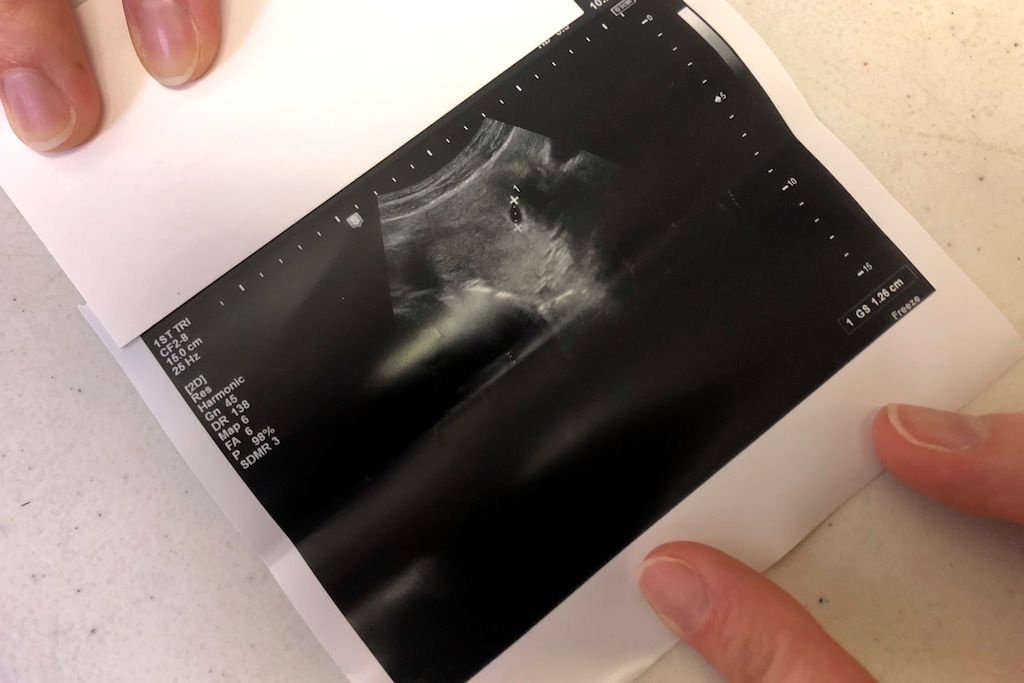

(AP Photo/Rebecca Santana) The ultrasound of a woman who went to the Hope Medical Group for Women on Feb. 20, 2020, in Shreveport, La. The clinic is one of three in the state that provides abortions to women, and it is challenging a state law that requires doctors who perform abortions to have admitting privileges at a nearby hospital. The Supreme Court is hearing the case on March 4.

If a picture featuring someone or something a half a planet away from us can trigger a powerful response, what about the filming of a woman’s own child, live in the mysterious world of her own womb? While ultrasounds have become so commonplace that their pictures won’t grace a Time photography list, they may be just commonplace enough to have the power to save the lives of babies targeted for abortion.

What happens to the psyche of a woman who sees her tiny child on the screen or print of an ultrasound? Though it is but miniature and still in the embryonic or fetal development stage, something about that experience can be literally life-changing and lifesaving.

Their approach is very straightforward. Perform a standard ultrasound. Factually explain what the mother is seeing and hearing. Inform her about resources available to her should she choose to not go through with the abortion. And here is the amazing statistic: even when encountering women who were dead-set on aborting when they walked out the abortion clinic, four out of five women who board a Stork Bus, see their baby on the ultrasound and hear the heartbeat, choose life.